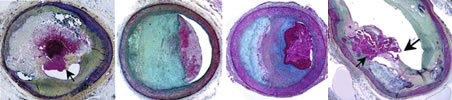

组图所示为动脉粥样硬化病变破裂,管腔血栓形成。

自左向右依次为:斑块破裂、斑块蚀损、钙化结节